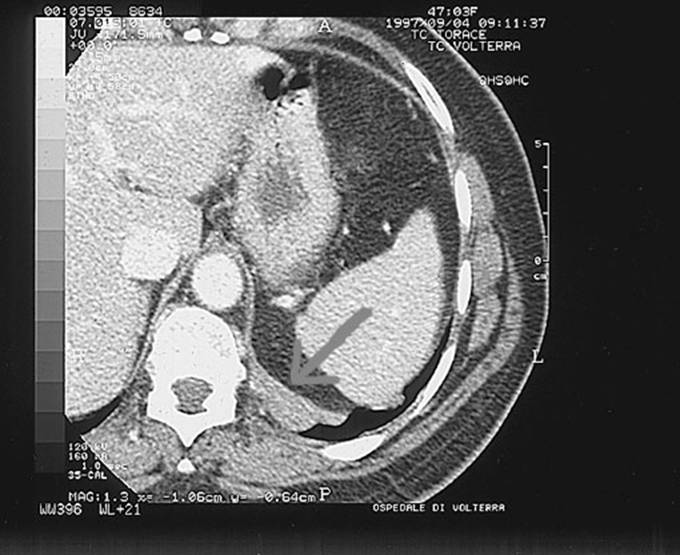

Mediastinal squamous cell carcinoma.

Figure1

Figure2